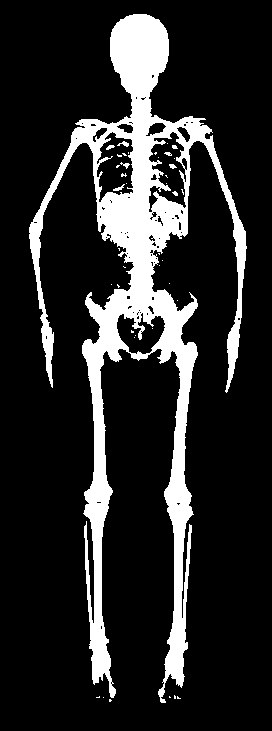

The key problem, however, is obtaining training data that simultaneously gives the inside and outside of the body in 3D. Most imaging technologies that simultaneously capture the inside and outside of the body use ionizing radiation, which is harmful to humans; e.g. Computed Tomography (CT) and X-rays. This means that such data is extremely limited, preventing learning-based methods. Our insight is to use dual-energy X-ray absorptiometry (DXA) data. DXA scans use low-dose X-rays to measure bone mineral density and body fat composition. The radiation level is so low that it is certified to be used on healthy patients for clinical studies, such as the UK Biobank [36]. In a DXA scan, two images are computed by combining two different energy levels: a soft-tissue image and a bone image (Fig. 2). In the silhouette of the body can clearly be seen, whereas reveals the structure and shape of the bones.

In our work, we use a simple heuristic to automatically segment the bone tissue in the bone images: we assume that the brightest pixels in each image belong to bone tissue. We empirically set for the male DXAs and for the female. As small artifacts remain (earrings, clothing, etc.), we remove small connected components with an area less than 50 pixels. Note that we do not claim to segment all bone tissues in the DXA images. While our segmentations are coarse, they capture the structure and location of the bones inside the body (as shown in Fig. 2); this is what we need to fit a 3D skeleton to them.

The presented metric has a limitation: predicting all the skin volume as bone would obtain a perfect result (, ). In Fig. 4 and Sup. Mat. we show that visually, OSSO’s predictions are coherent and match the DXA bone images better than Anatomy Transfer. In Sup. Mat. we provide examples of subjects with high Body Mass Index, for which Anatomy Transfer predicts a stretched skeleton, while ours are closer to the DXA skeleton mask.